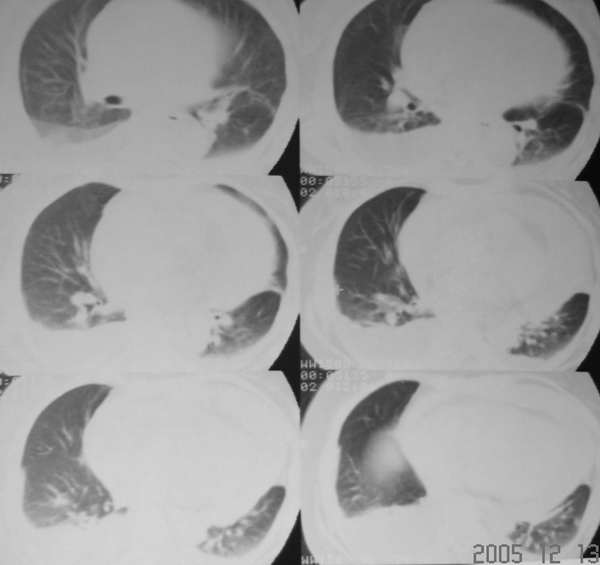

f43y昨日突发胸剧痛,今下午来医院并行ct平扫示:左下肺少许淡薄渗出病灶,双侧胸腔积液以右肺为甚,心包积液。

我认为,一般情况胸腔积液与心包积液并没有相关性,我们经常看到胸腔积液,但心包积液比胸腔积液要少。而这个患者心包积液较重,且发病较急,存在心包填塞的表现,右心房增大,说明回心血流受阻,肺淤血,可能会导致胸腔积液。该患者心包积液较重,建议进一步增强扫描。

患者急性起病,影象学表现为大量心包积液和双侧胸腔积液,心包积液密度较高,应该考虑为积血,患者没有外伤史,自发性心包积血应该想到主动脉夹层动脉瘤心包内部分破裂的可能,主动脉根部明显增粗也支持该诊断。关于胸腔积液有两种可能的解释,一是由于夹层的压力很高,造成血性胸腔渗出;另外就是由于心包填塞造成腔静脉系统压力增高,引起胸腔的渗出改变。

心包大量积液,双侧行腔积液,升主动脉增宽,结合突然发病,不排除主动脉夹层破裂。

心包及胸腔积液,双下肺血管增粗,以右下肺为著,考虑肺淤血